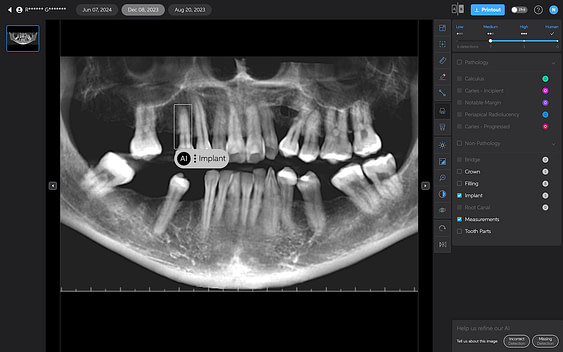

Pearl is the company, and the platform is called Second Opinion. This browser-based platform integrates with your imaging software or PMS to upload any 2D radiographs taken automatically. Once on the platform, it reads the images and provides you with diagnostic information.Second Opinion positions itself as a "second set of eyes" for dental professionals. It uses AI to analyze radiographs and highlight potential areas of concern. The platform aims to help identify a range of dental conditions, from caries and calculus to bone loss and periapical radiolucencies.

Second Opinion designed its interface with simplicity and efficiency, aiming to integrate seamlessly into dental workflows. It really looks great, is easy to use, and, more importantly, is nice to show patients.

Overall, the design of Second Opinion's interface and image management features is really well done. It is one of the best AI platforms I have seen. It is very easy to use, and the UI looks modern and futuristic. As with any new system, there will likely be a learning curve as teams adjust to incorporating it into their daily routines.

AI Detections

The cornerstone of Second Opinion's offering is its AI-powered detection system.

Pearl currently only analyzes 2D radiographs, including intraoral radiographs and OPGs. 3D X-ray analysis is under development and is scheduled for release later in 2025.

Second Opinion aims to assist dental professionals in identifying a range of dental conditions by automatically highlighting areas of potential concern. However, it's crucial to remember that the accuracy of AI detections can vary, and dental professionals must be able to evaluate these suggestions critically.

Pearl’s Second Opinion can report on six conditions on 2D x-rays at this stage. Let's go over each one of the AI detections below:

- It detects a ‘notable margin’ on an implant crown that is just the abutment-crown joint.

- Or calls a natural tooth an implant